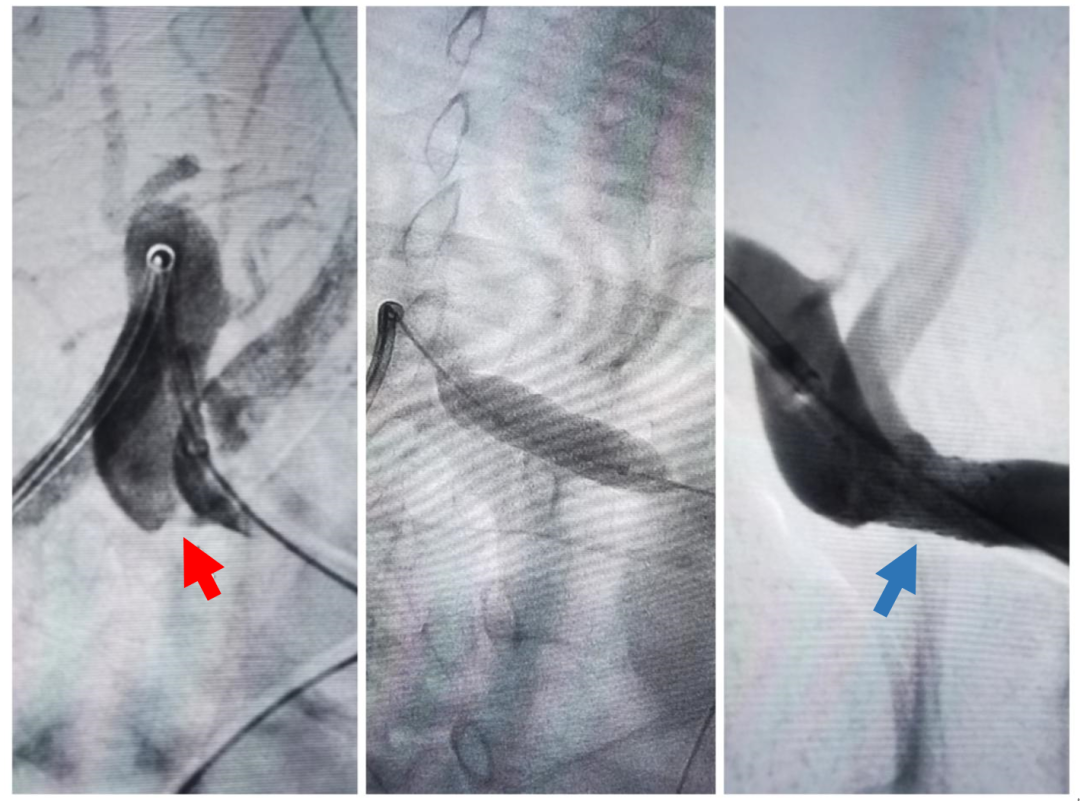

DSA:右侧锁骨下动脉起始段重度狭窄(红箭头),球扩支架顺利置入狭窄解除(蓝箭头)

全脑血管造影提示:右侧锁骨下动脉重度狭窄,同期行右侧锁骨下动脉支架置入术,手术过程顺利,无不良反应,整个手术用时不到1小时。